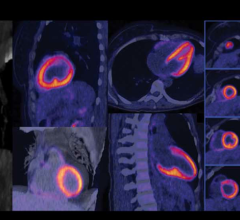

Zebra Medical Vision and Clalit Health Services announced the completion of two research projects that allow early identification of patients with bone and cardiovascular disease. Using existing computed tomography (CT) data, Zebra-Med’s algorithms allow Clalit to identify patients at risk of osteoporotic fractures and cardiac events. Both research projects were independently validated by the Clalit Research Institute and will be presented for the first time during the 2018 Radiological Society of North America (RSNA) annual meeting, Nov. 25-30 in Chicago.